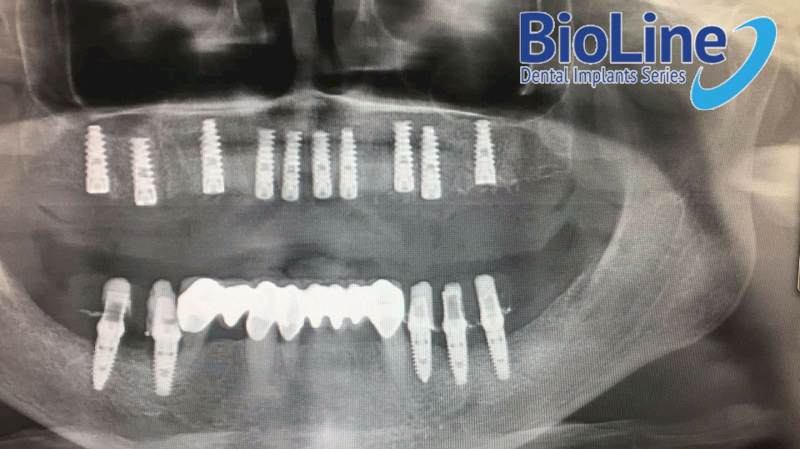

Nhờ vào thiết kế tối ưu, đa dạng hình dáng và kích thước, Implant BioLine phù hợp với mọi đối tượng mất răng, bao gồm mất răng đơn lẻ, mất nhiều răng hay mất răng toàn hàm.

Trụ Implant BioLine tồn tại vững chắc trong xương hàm ở mọi vị trí mất răng